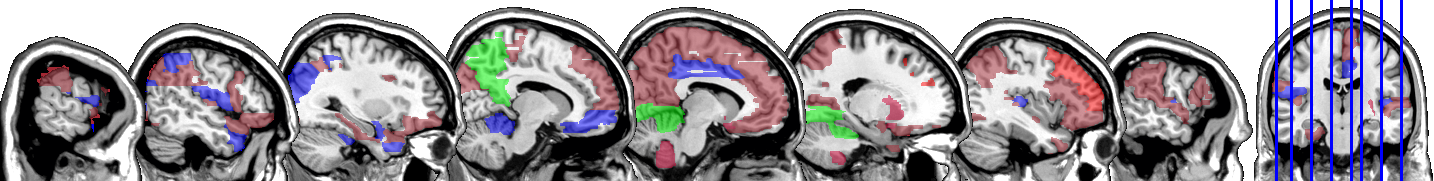

One motivating example for our methods is the application to the functional magnetic resonance imaging (fMRI). The dataset consists of the functional signals of the brain activities measured by blood-oxygen-level-dependent (BOLD), which detects hemodynamic changes based on the metabolic demands followed by neural activities. There are pre-specified regions of the brain, and the BOLD signals associated with multiple voxels in each region are integrated into one signal for that region. Thus, the fMRI data are considered to be multivariate functional data in which each functional predictor represents the signals from a region of the brain. In Section 8, we regress the ADHD index to the regional BOLD activities of the fMRI of the human subjects. There are regions of the brain in the data, and our methods reduce the regions to 41 regions with significantly lower errors than the linear functional regression. Figure 1 displays the regions of the brain’s atlas that are identified by our method. It shows that the methods simplify the data analysis and provide clear representation while keeping the crucial information. The analysis shows that there is an urgent need for new methods in the fields of medical and life sciences as well as other related areas.

In Figure 4 and Figure 5, we display the regions associated with the estimated active sets for IQ and ADHD by the MFG-LASSO respectively. The final active sets of the algorithms were extracted, and matched with the AAL’s atlas where each of the regions has a label. The regions were manually entered into the WFU picked atlas Maldjian and et al. (2003) tool of the SPM-12 ran on MATLAB 2020b to produce mask.nii files. The mask files were imported on MRIcron software to produce the multi-slice images.

The active sets cover the regions associated with IQ in Yoon and et al. (2017) such as cerebello-parietal component and the frontal component. It is mentioned in the paper that the parietal and the frontal regions are strongly associated with intelligence by maintaining a connection with the cerebellum and the temporal regions. The shaded areas cover the ones mentioned in Goriounova and Mansvelder (2019) as well. We provide the name of the regions associated with these active sets in the appendix.

It is interesting that ADHD and IQ have a large proportion of common active sets. For instance, when MFG-LASSO is applied, they overlap in ROIs where the size of active sets are and for IQ and ADHD respectively. On the other hand, the ROIs that are associated with ADHD but not with IQ are the middle and superior frontal, the Parahippocampal, the inferior parietal, and the superior temporal pole gyri. The ratio of the number of right hemisphere regions to the left ones associated with IQ is significantly greater than that of ADHD.